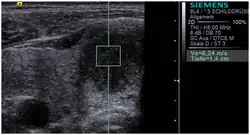

Conventional ultrasonography (lower image) and elastography (supersonic shear imaging; upper image) of papillary thyroid carcinoma, a malignant cancer. The cancer (red) is much stiffer than the healthy tissue.

Scale is in kPa of Young's modulus